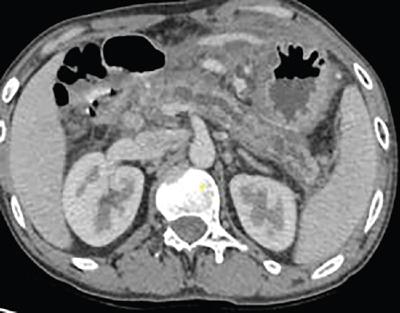

Shrinivas B. Desai, Ritu K. Kashikar, Shreya Shukla Radiological signs are classical and distinctive abnormalities characteristic of a disease. These can be seen on any imaging modality. Resemblance to commonly seen objects and patterns form the basis of radiological signs. The aim is to help the reader associate, understand and memorize these pathologies with the aid of signs. Various signs pertinent to hepatobiliary system are described in the chapter. Described on MRI when liver lesion shows a peripheral rim of high T2 signal intensity with the centre of the lesion appearing isointense to the background of noncirrhotic liver on T2WI mimicking an atoll. It is considered a characteristic sign of an inflammatory hepatic adenoma (image) but is only seen in about one-third of cases Extrinsic smooth impression over medial aspect of duodenum along its posteroinferior aspect, seen in pancreatic head pathologies like carcinoma. This sign is seen in pancreatic adenocarcinoma Presence of a persistently hyperattenuating dot within a lesion on arterial and portal venous CT. This corresponds with peripheral nodular enhancement seen on dynamic MR. Presence of bright dot suggests that the lesion is a hemangioma and helps in ruling out metastasis Ultrasound appearance of multiple cystic spaces or lesions that has been used to describe the appearance of an intraductal papillary mucinous neoplasm of the pancreas. Seen on contrast CT in portal hypertension. The appearance is based on resemblance to Medusa from Greek mythology. Dilated engorged paraumbilical veins radiating across umbilicus to join systemic veins is seen. This sign is seen in Caroli’s disease on contrast CT. Enhancing dots within dilated intrahepatic bile ducts represent portal radicles. Caroli’s disease Irregularly dilated pancreatic duct with multiple strictures and intervening dilatation with associated dilated side ductules resemble multiple lakes supplied by a single territory. Best seen in MRCP images. Chronic pancreatitis It is a finding on MRI and CT and is best seen on MRI T2-weighted and postcontrast T1-weighted sequences. Small necrotic/purulent areas in the pyogenic abscess ‘cluster’ together and then coalesce into a larger necrotic/purulent areas, eventually becoming a larger septated abscess cavity. At the periphery of these clusters: Associated with pyogenic hepatic abscesses and can help differentiate pyogenic abscesses from other types of liver lesions Abrupt termination of gas within the proximal colon at the level of radiological splenic flexure. The inflammatory exudates in pancreatitis extend to the phrenicocolic ligament giving rise to this sign Seen on grey scale ultrasound as a reverberation artifact when small calcific or highly reflective objects are imaged. The colour comet-tail artifact is an ultrasonographic sign seen in a number of situations when colour Doppler scanning is performed. This sign occurs in cases of traumatic right-sided diaphragmatic rupture with resultant partial herniation of liver through the defect. Separation of the herniated liver from its intra-abdominal component is via a small constriction at the level of diaphragm resembling a cottage loaf. Cottage loaf is a particular shape of bread in which larger and smaller roughly spherical balls are squashed together. Traumatic right-sided diaphragmatic rupture with resultant partial herniation of liver Bile eccentrically outlines luminal stone, creating a low attenuation crescent. Best seen on MRCP images. Choledocholithiasis Dilatation of both pancreatic duct and CBD is referred to as the double duct sign. Positive double duct sign suggests the diagnosis of carcinoma of the head of the pancreas and ampullary tumours and is hence considered ominous. Occasionally the sign may be seen in impacted gallstone in the distal duct. This feature is seen in patients with liver abscess on contrast-enhanced CT. A double, inner hyperattenuating and outer hypoattenuating rim is seen surrounding the hypodense abscess. The inner hyperattenuating rim corresponds to the enhancing abscess membrane, while the outer rim corresponds to the edema of the surrounding liver which appears hypodense and may show delayed enhancement. Liver abscess A positive duct penetrating sign is when a mass is penetrated by an unobstructed pancreatic duct; this makes focal pancreatitis the most likely cause rather than pancreatic carcinoma. This sign is best appreciated on MRCP (or ERCP). A radiographic sign that can be useful in differentiating between focal pancreatitis (inflammatory pancreatic mass) from pancreatic carcinoma. The duct-penetrating sign on MRCP is more helpful in differentiating between these two entities than a delayed enhancement pattern on CT or MRI It occurs when there is both limy bile and a gallstone in the common bile duct. The linear vertical radiopaque bile forms the line of the exclamation mark (i.e. !), whilst a more distal calculus forms the ‘dot’ at the end of the exclamation mark. Pathognomonic imaging sign of the rare diagnosis of limy bile on plain abdominal radiography Nonenhancing ruptured lesion with peripheral rim enhancement showing discontinuity from the rest of the liver and protruding from the liver surface is called the enucleation sign. Ruptured HCC Enlargement of the pericholecystic space. One of the signs of liver cirrhosis Can be seen on technetium 99m sulphur colloid scans of the liver and spleen, as well as CT studies. It occurs as a focal area of increased radiopharmaceutical uptake in the medial segment of the left hepatic lobe (segment IV) occurring as a result of SVC obstruction and portosystemic venous shunting between the superior vena cava and the left portal vein via the internal thoracic and paraumbilical veins. The equivalent of this sign may also be seen on contrast-enhanced CT scans as a hypervascular region. Budd–Chiari syndrome causes the hot spot sign in the caudate lobe

16) The double target sign